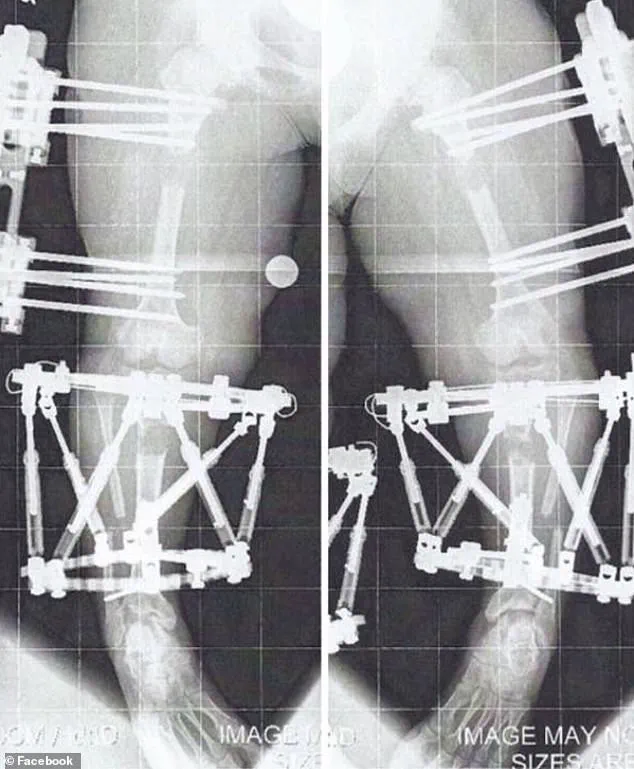

The surgery, which targets the thigh or shin bones, involves implanting either an external fixator or an internal rod to slowly pull the bone segments apart over weeks or months.

The process involves surgically cutting the bone and implanting either an external fixator or an internal rod to gradually lengthen the limb.

This procedure, which involved fixators implanted in her humerus (the upper arm bone) in January 2012, allowed her to remain mobile during the process.